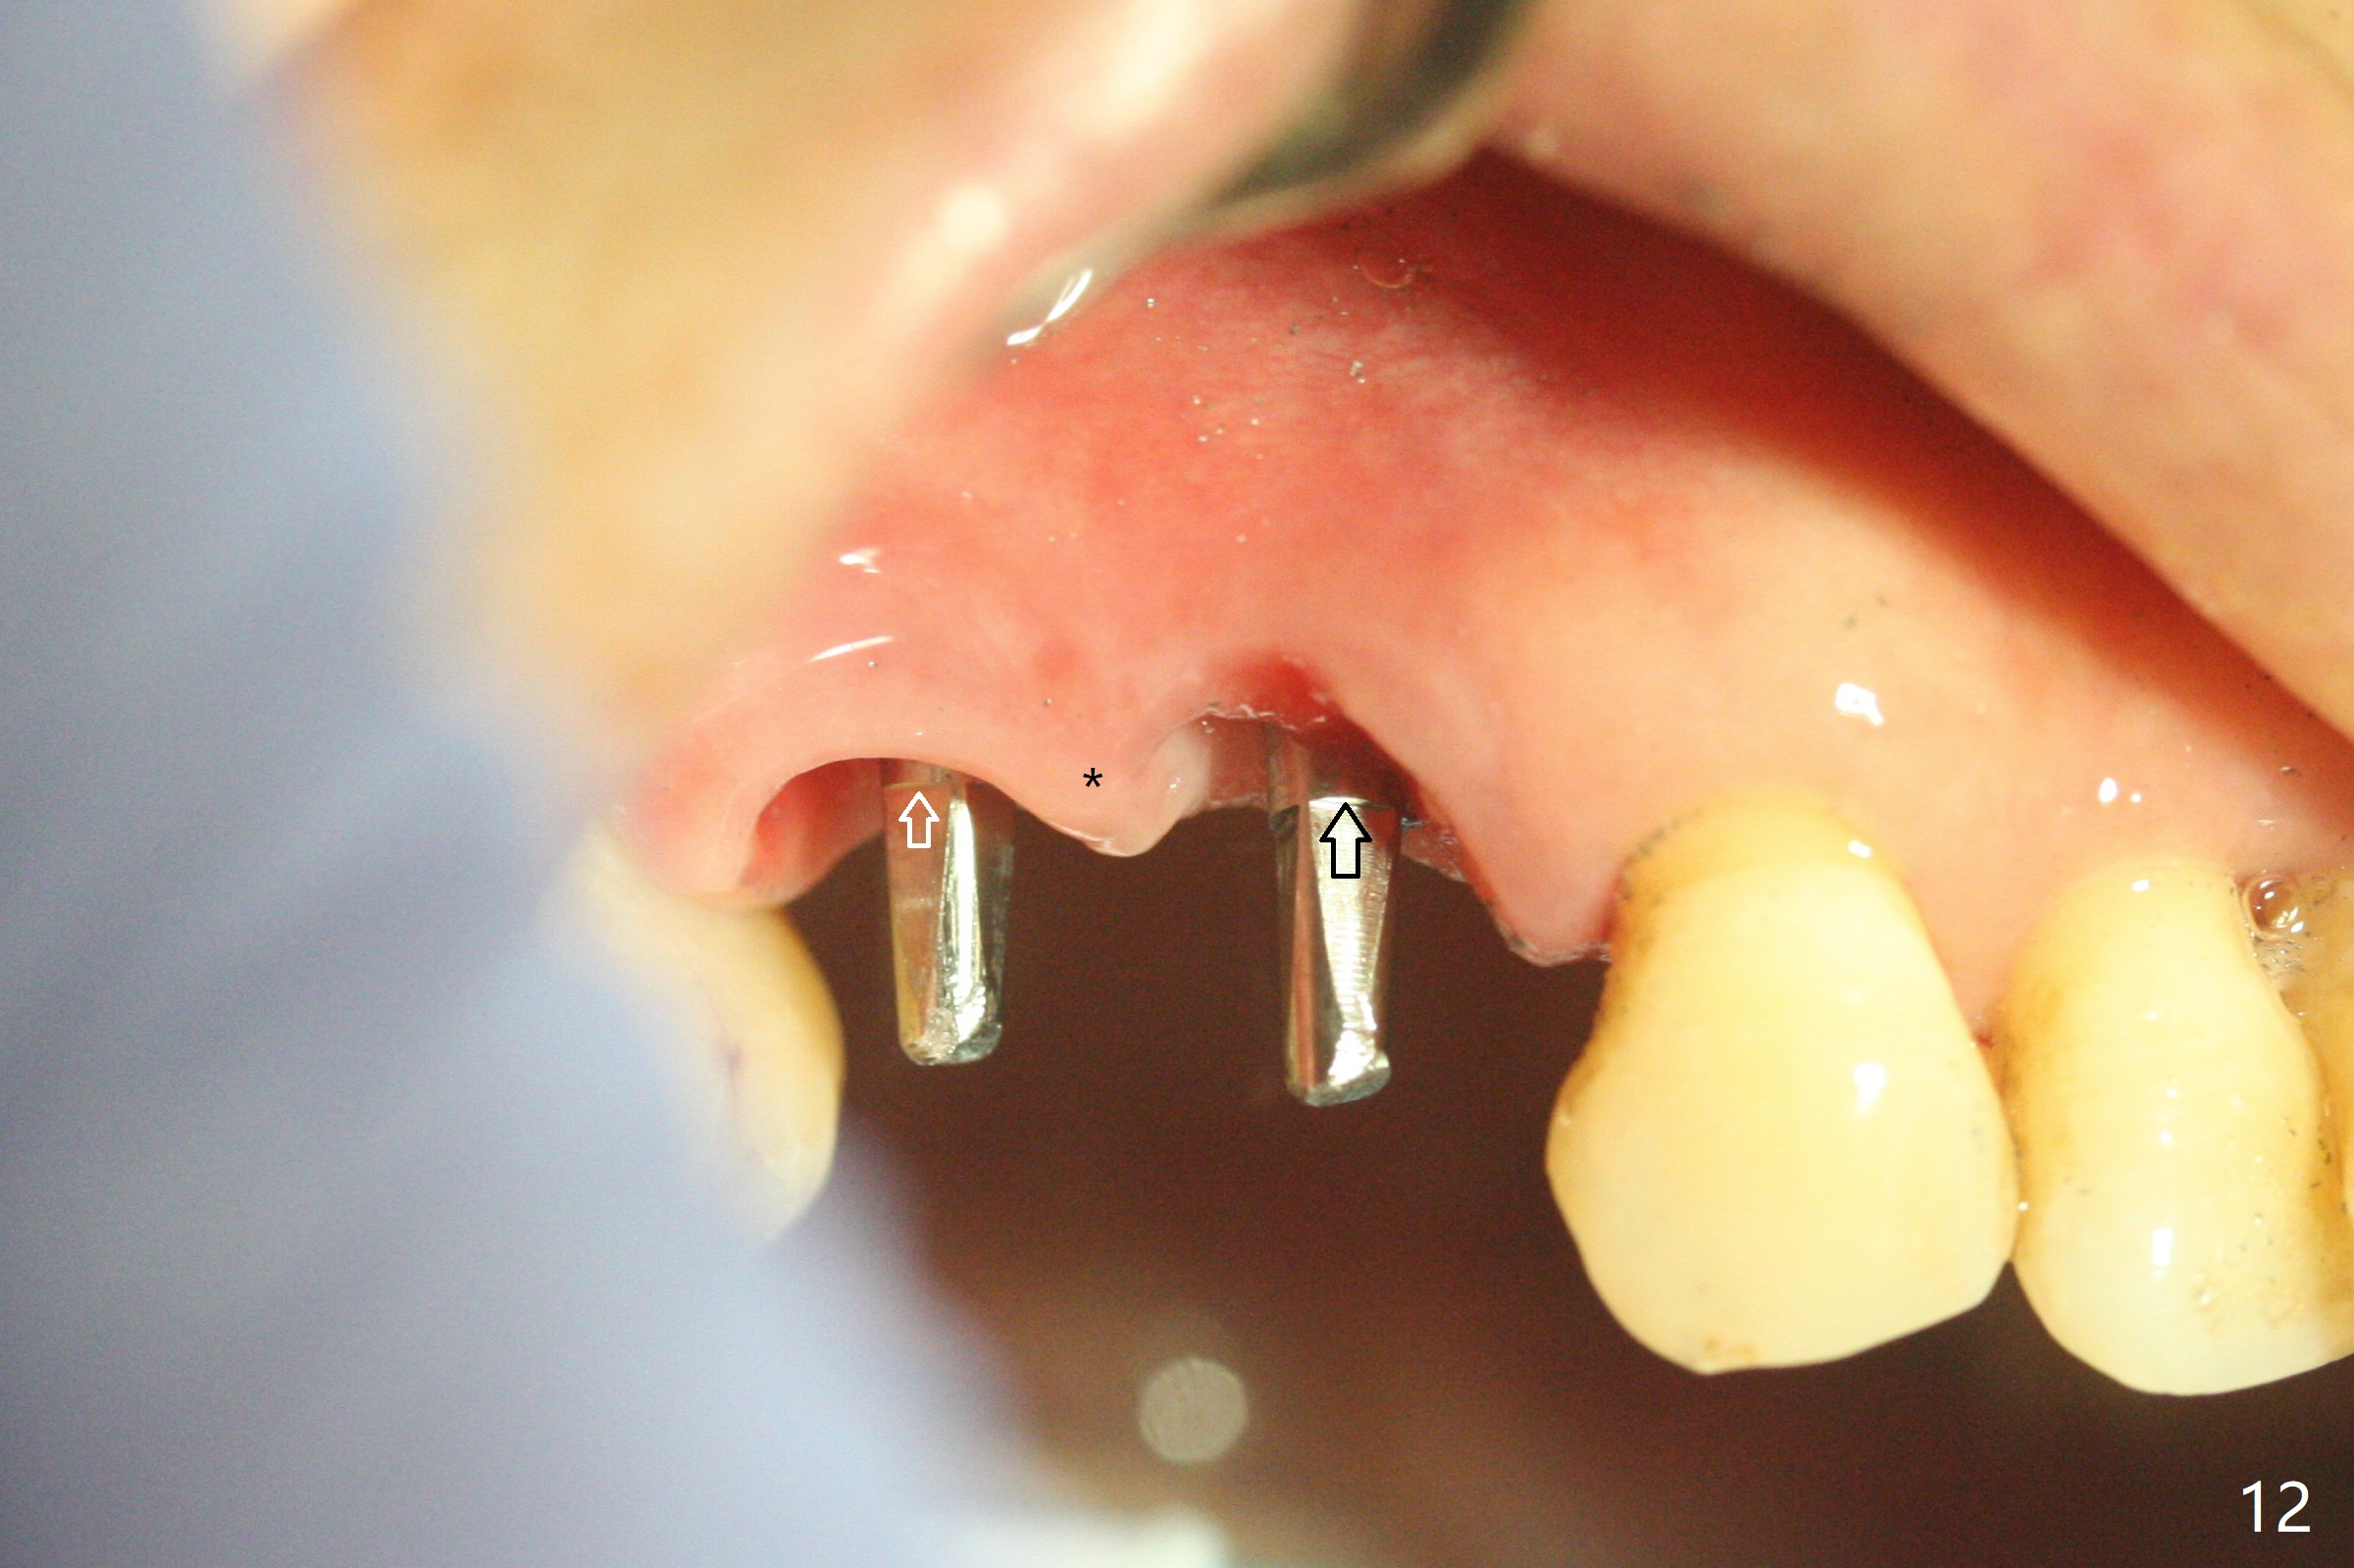

术前CT显示右上4牙槽骨比5窄(图一,二),3.5毫米植体比较合适,况且牙龈厚,基台长的一段式植体显得得当。为了取得最好的植体方位,4先拔除(图三),种植(图四),调整后者深度后,拔除5(术前征求病人同意),开始钻洞(图五),完成种植(图六)。粘性骨粉不仅放置于植体周围,而且6牙根近中(图七),4/5牙槽嵴和龈乳头(P)之间,减少术后龈乳头萎缩(图八:*)。制作两个分开临时牙冠,有利于维持龈乳头。对于病人来说,临时牙冠帮助咀嚼,而对侧拔牙创无法吃饭。术后3个月两个分开临时牙冠(其中一个龈方移位(图九:箭头)保持龈乳头(*)和牙龈外形(图十:*)。临时牙冠取出后,调整基台高度,少量钛屑(不妨大局)附着在健康的牙龈沟(图十一),再次显示两个基台之间龈乳头(图十二:*),衬里,修整的临时牙冠又插回牙龈沟(图十三:箭头),继续维持软组织形态,准备一个月后,调整基台边缘(图十二:箭头),取模。术后五个月大部分骨粉依然保留在植体和邻牙周围,龈乳头退缩不多(图十四: P)。三个月后(术后六个月)钛削无影无踪(图十五,与图十一对比))。永久性牙冠周围空间慢慢会消失(图十六,使用临时性胶水)。